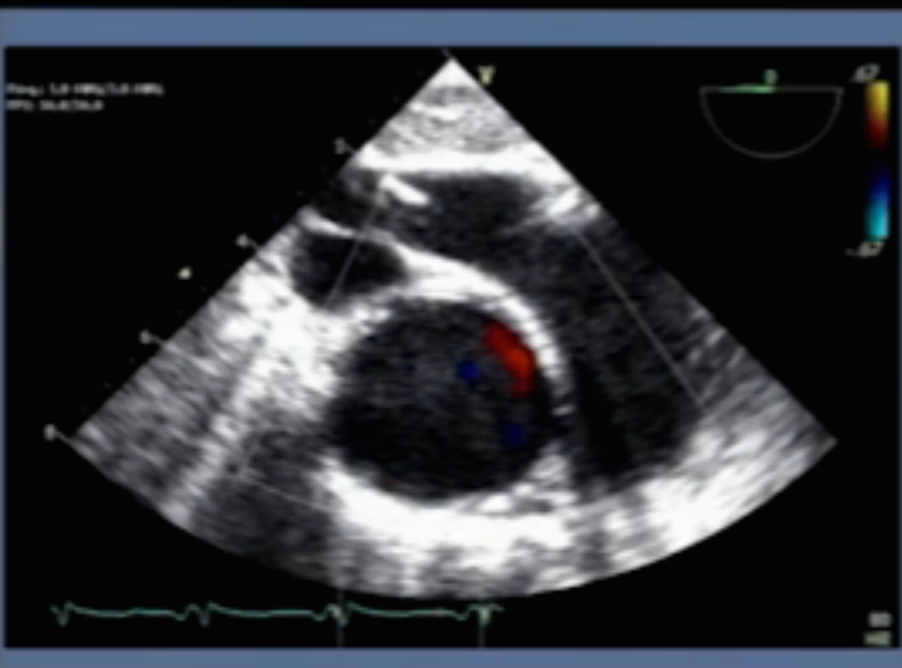

name the structures in this TEE view (HE)

Ao, SVC, Main PA, RPA (hugging Ao), LPA